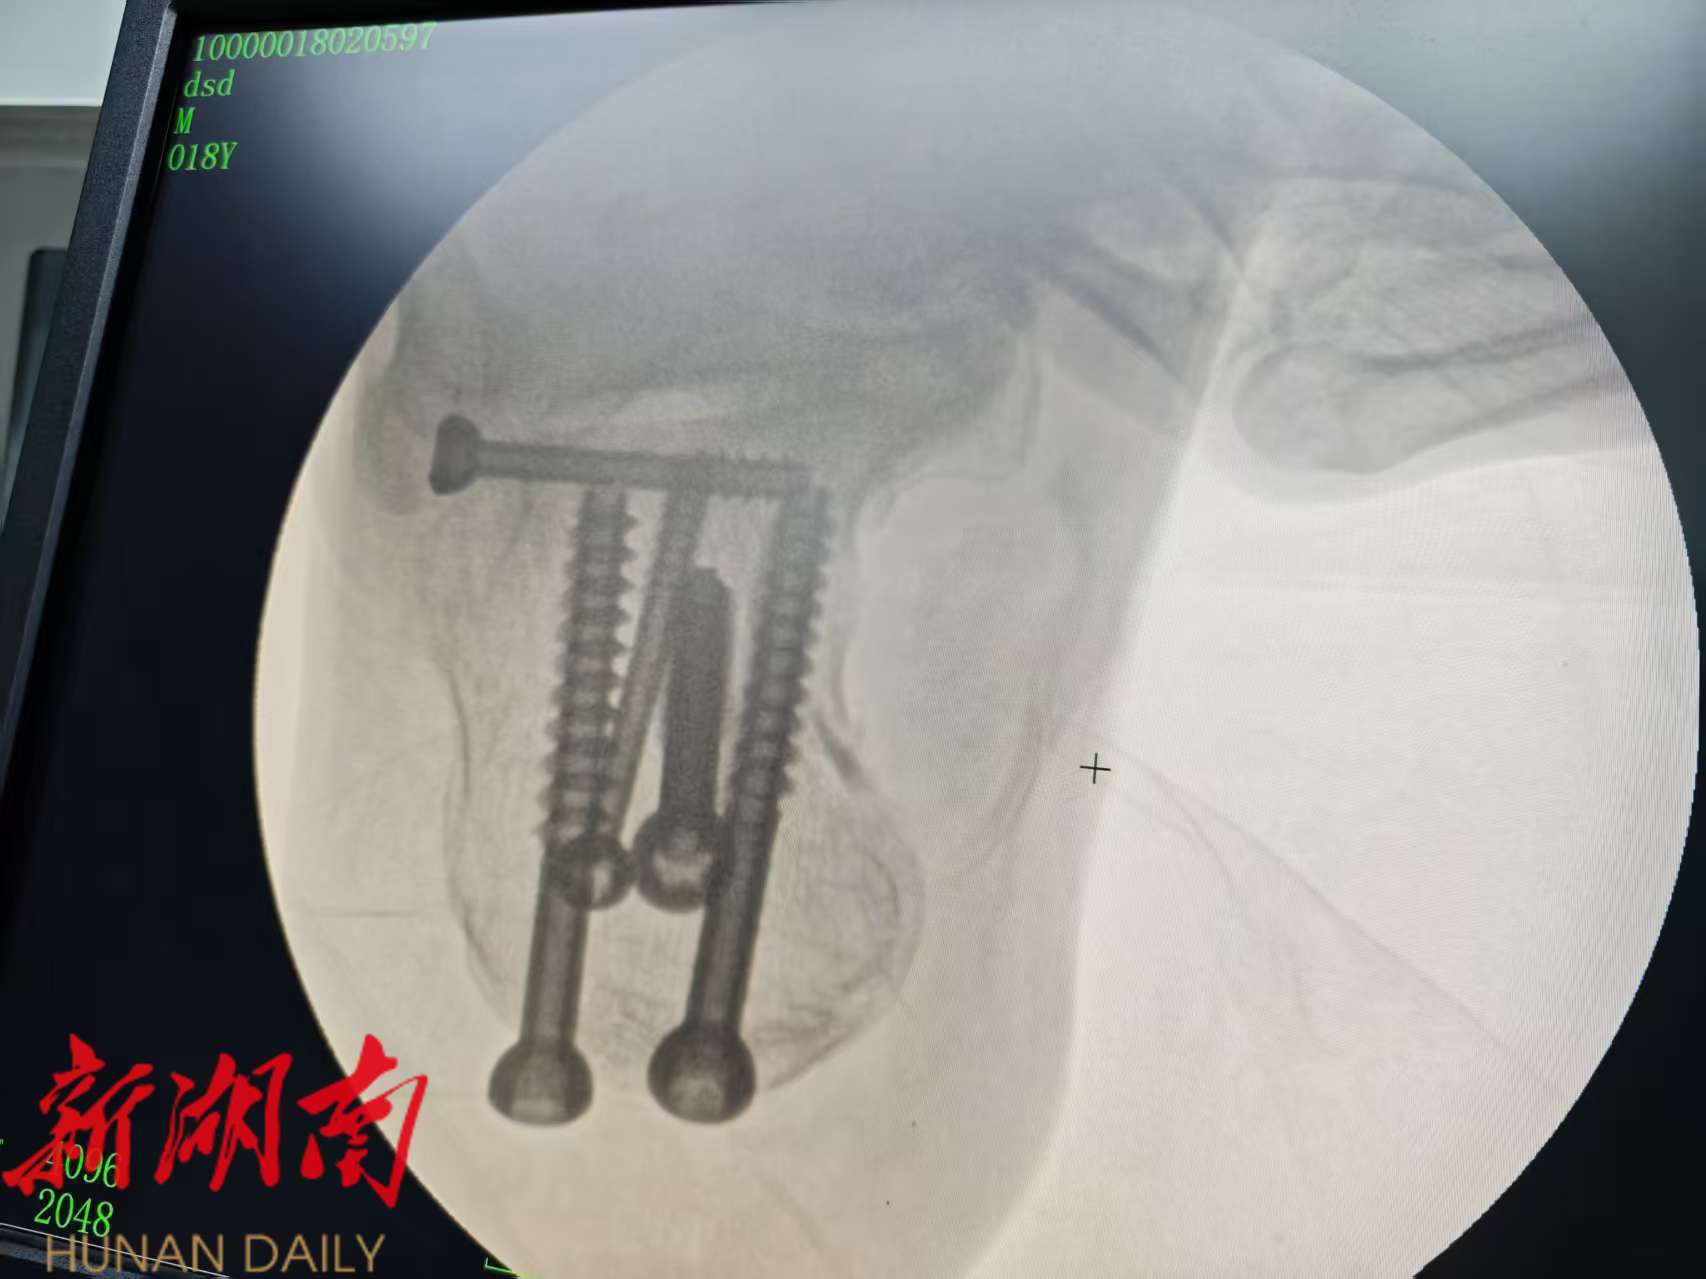

为最大限度减轻患者痛苦、降低并发症风险并促进早期功能康复,湖南医药学院总医院专家,中方县人民医院骨科挂职科主任秦溢主任在充分评估患者伤情后,决定采用创伤更小、技术要求更高的“闭合复位微创内固定术”。术中,在C型臂X光机的实时精准引导下,秦溢 通过5个微小的皮肤切口,利用撬拨、牵拉、挤压等手法将骨折块进行微创复位,恢复关节面的平整性及跟骨的高度,长度和宽度,并经皮置入螺钉坚强固定骨折端。整台手术过程顺利,出血量仅5毫升。

术后患者生命体征平稳,足跟部肿胀明显减轻,疼痛感显著缓解。由于手术创伤小,患者第二天即可在医生指导下进行足踝部的非负重功能锻炼,极大地缩短了卧床时间,加速了康复进程。患者及家属对手术效果和医院的精心治疗护理表示非常满意。